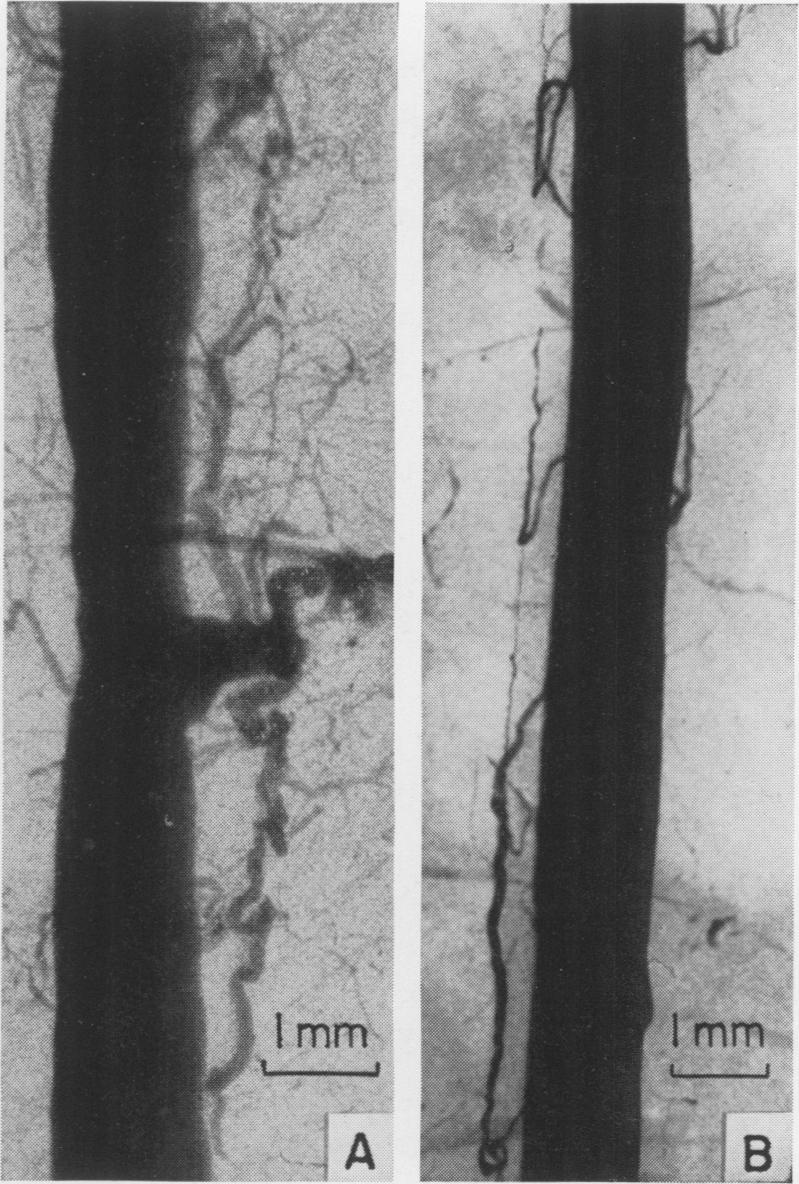

Vascular channels established by implantation of a systemic artery into the myocardium.